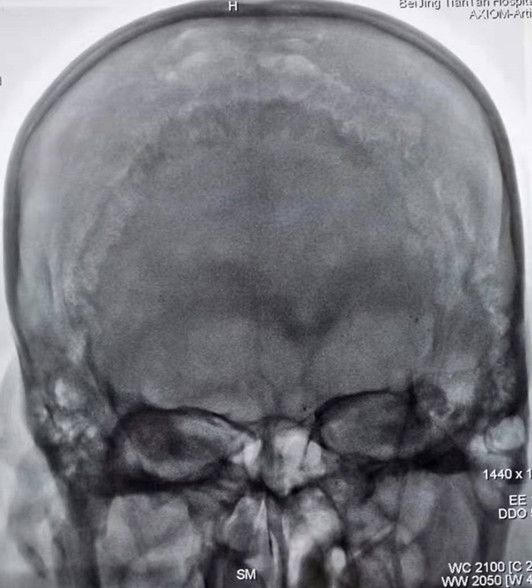

术前影像

图1急诊颅脑CT